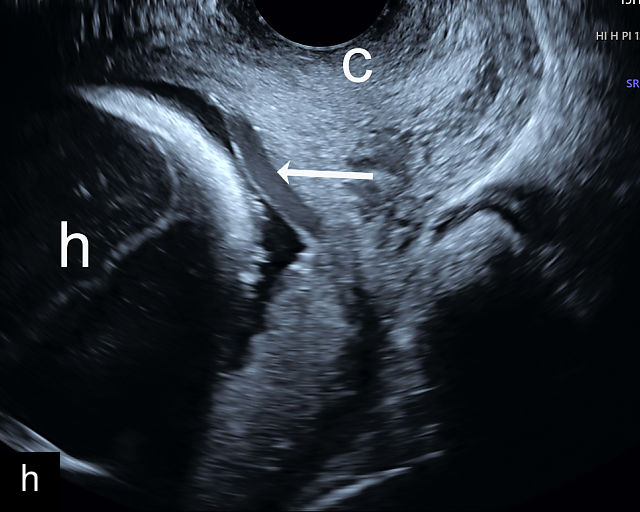

5

Placenta previa and low-lying placenta. (a) Transabdominal grayscale ultrasound image suspicious for placenta previa. The placenta (PL) appears to overlie the internal cervical os (CX). Note the time stamp: 2:19:37. (b) Transvaginal ultrasound of the same patient taken approximately 50 minutes later. Note the time stamp: 3:10:25. The internal os and the lower placental edge are both clearly seen, and the placenta does not overlie the internal os. Because the lower placental edge is 1.93 cm from the internal os, it will likely resolve by the third trimester. (c) Transabdominal grayscale ultrasound of placenta previa. The placenta (p) covers the cervix, but the cervix, especially the internal os, cannot be visualized due to shadowing. (d) Transabdominal grayscale ultrasound of placenta previa. The placenta (p) covers the cervix (c) but shadowing obscures adequate visualization. The internal os is indicated by the arrow. (e) False-positive image of placenta previa on transabdominal grayscale ultrasound. The bladder (b) is full, pushing the anterior and posterior walls of the lower uterine segment (ls) together making it appear that the placenta (p) overlies the internal os of the cervix. In reality, the line depicted by the arrowheads is where the anterior and posterior walls of the lower segment are in proximity to each other. The cervix is much lower and is obscured by shadowing (c). (f) Transabdominal grayscale ultrasound image of placenta previa. The placenta (p) covers the cervix (c), but the cervix, especially the internal os, cannot be visualized due to shadowing. b, bladder. (g) Transvaginal grayscale ultrasound image of placenta previa. The placenta (p) completely covers the internal os (arrow) of the cervix (c). The internal os can be seen clearly. h, fetal head. (h) Transvaginal grayscale ultrasound image of posterior low-lying placenta (p). The lower placental edge is clearly seen and is 1.56 cm from the internal os (arrow) of the cervix (c). The placental edge and the internal os are clearly seen. h, fetal head. (i) Transvaginal grayscale ultrasound image of a posterior placenta previa (p). The internal cervical os is clearly seen (arrow). c, cervix. (j) Transvaginal grayscale ultrasound image of an anterior placenta previa (p). The internal cervical os is clearly seen (arrow). c, cervix; h, fetal head. (k) Transvaginal grayscale ultrasound image of a posterior placenta that was thought to be low-lying on transabdominal sonography but could not be adequately assessed. This examination clearly shows the lower edge of the placenta (p) to be 2.18 cm from the internal os (arrow) of the cervix, firmly establishing that the placenta is not low-lying and allowing the patient to undergo labor safely and deliver vaginally. c, cervix. (l) Transvaginal grayscale ultrasound image of placenta previa. The placenta (p) completely covers the internal os (arrow) of the cervix (c). The internal os can be seen clearly.